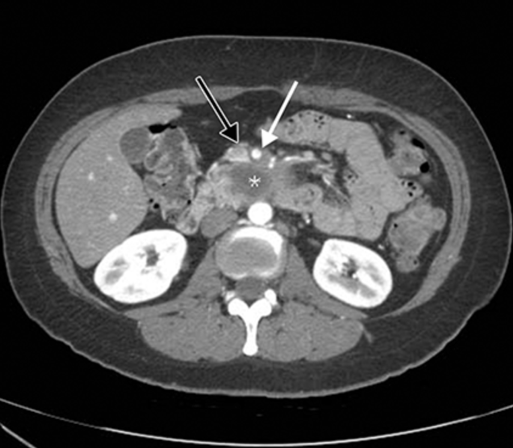

CT:

Most lethal solid tumor; Highest incidence after age 60

• o Risks: smoking, chemical exposure, high meat/fat diet, diabetes, chronic pancreatitis

• o KRAS activating mutations; Tumor suppressor mutations in p16, TP53, SMAD4

• o Precursor to cancer: pancreatic intraepithelial neoplasia

• o Sx:

• • Anorexia, wt loss

• • Abdominal/back pain

• • Jaundice

• • Migratory thrombophlebitis (troussea’s sign)—hypercoagulability and tendency to venous thrombosis

• o Derived from ductal cells; spreads by lymphatics and along nerves

• o 5 year survival=5% (only 20% are surgical candidates)

• o Gross: firm, gray poorly demarcated mass. Invasion of peripancreatic tissue and local structures common

• o Microscopic: >75% are well-moderately differentiated, prominent desmoplastic rxn, perineural invasion